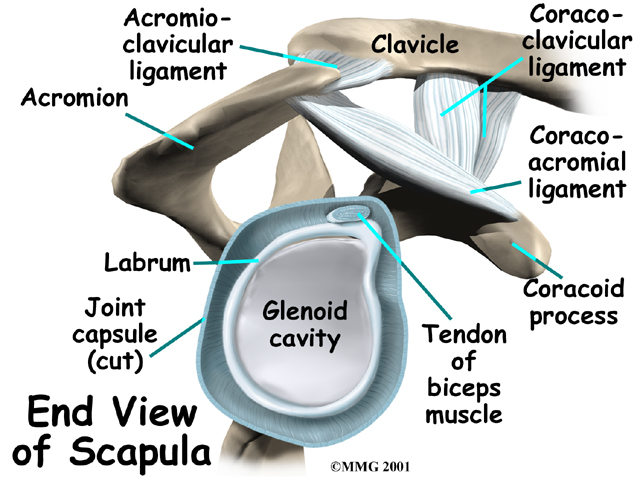

Tendons attach muscles to bones. Muscles move the bones by pulling on the tendon that they attach to. The rotator cuff muscles help raise and rotate the arm. As the arm is raised, the rotator cuff also keeps the humerus tightly in the socket. The socket of the shoulder is part of the scapula bone and is called the glenoid fossa. The glenoid fossa is very shallow and flat so without the rotator cuff muscles the top part of the humerus (the head) would slide out of the centre of the fossa.

The part of the scapula that connects to the lateral shoulder is called the acromion. A bursa is located between the acromion and the rotator cuff tendons. A bursa is a lubricated sac of tissue that cuts down on the friction between two moving parts. Bursae are located all over the body where tissues must rub against each other. In this case, the bursa protects the acromion and the rotator cuff from grinding directly against each other.

The humeral head of the shoulder is the ball portion of the shoulder joint. The humeral head has several blood vessels, which enter at the base of the articular cartilage. Articular cartilage is the smooth, white material that covers the ends of bones in most joints. Articular cartilage provides a slick, rubbery surface that allows the bones to glide over each other as they move. Cartilage also functions as a shock absorber in the joint.

A watertight sac called the joint capsule surrounds the shoulder joint. The joint capsule holds fluids that lubricate the joint. The walls of the joint capsule are made up of ligaments. Ligaments are connective tissues that attach bones to bones. The joint capsule has a considerable amount of slack (loose tissue), so that the shoulder is unrestricted as it moves through its large range of motion.